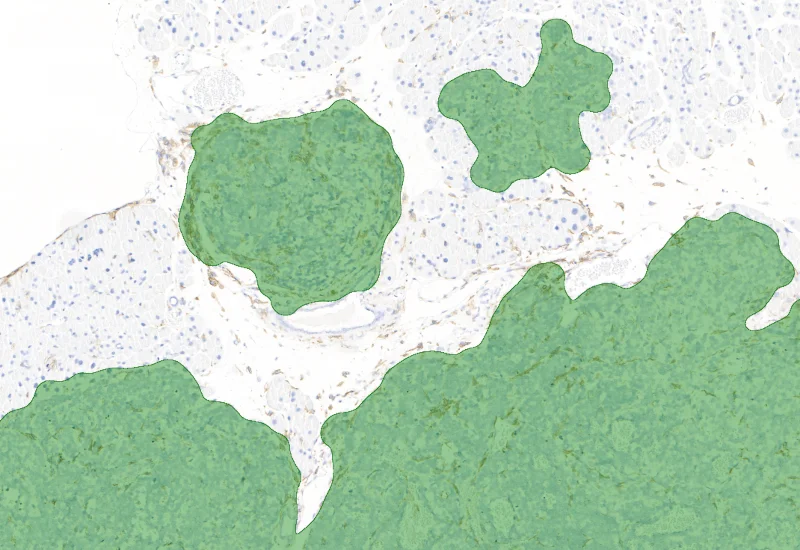

IHC Tumor Macrophages

Segment tissue into tumor and healthy areas, detect CD68+ macrophages, and quantify macrophage area within each tissue compartment.

The IHC Tumor-Macrophages APP provides tissue detection including separation into tumor tissue and healthy tissue. It detects macrophages based on a specific staining (e.g. CD68). The APP outputs the area of macrophages within tumor tissue and healthy tissue.

Image courtesy of Dr. Patrick Michl, Dr. Maren Egidi and Dr. Heidi Griesmann, Universitätsklinikum Halle (Saale)

Macrophage/Tumor detection